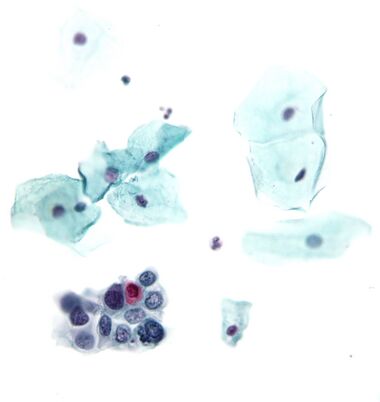

عادةً ما تبحث اختبارات عنق الرحم عن تشوهات في الظهارة / حؤول / خلل التنسج / تغيرات حدودية ، وكلها قد تشير إلى CIN. النوى سوف تلطخ باللون الأزرق الداكن ، والخلايا الحرشفية سوف تلطخ باللون الأخضر والخلايا الكيراتينية سوف تلطخ باللون الوردي / البرتقالي. يمكن ملاحظة الخلايا الكويلية حيث يوجد بعض خلل التنسج (في الظهارة). عادة ما تكون نواة الخلايا الكويلية غير منتظمة ، مما يشير إلى سبب محتمل للقلق ؛ تتطلب المزيد من التَحَرٍّ والاختبارات التأكيدية.[بحاجة لمصدر]